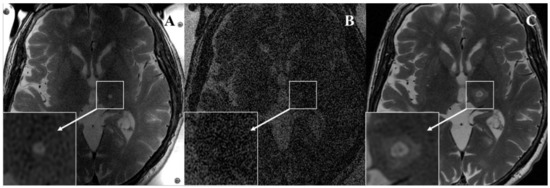

| 2ch-FUS | Body-RF | 8ch-HEAD | p Value 2ch-FUS vs Body-RF | p Value 2ch-FUS vs 8ch-HEAD | k Value (95% CI) | |

|---|---|---|---|---|---|---|

| Zone I | ||||||

| Present | 0.82 (0.59, 1.00) | |||||

| Reader 1 | 6 (75.0) | 0 (0) | 8 (100) | 0.031 | 0.500 | |

| Reader 2 | 8 (100) | 0 (0) | 8 (100) | 0.008 | 1.000 | |

| Zone II | ||||||

| Present | 0.90 (0.71, 1.00) | |||||

| Reader 1 | 8 (100) | 1 (12.5) | 8 (100) | 0.016 | 1.00 | |

| Reader 2 | 8 (100) | 0 (0) | 8 (100) | 0.008 | 1.00 | |

| Zone III | ||||||

| Present | 0.91 (0.75, 1.00) | |||||

| Reader 1 | 3 (37.5) | 2 (25.0) | 8 (100) | 1.000 | 0.063 | |

| Reader 2 | 3 (37.5) | 3 (37.5) | 8 (100) | 1.000 | 0.063 |